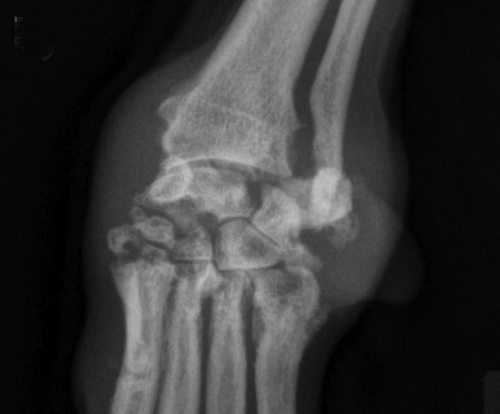

In a November 2016 article, a team of Wisconsin and Michigan researchers studied the clinical records of 79 dogs diagnosed with immune-mediated polyarthritis (IMPA). Of those 79 dogs, 13 had erosive IMPA, of which, two were cavalier King Charles spaniels. The 13 affected dogs had erosive lesions in their carpal joints. The estimated median synovial fluid lymphocyte count for dogs with erosive IMPA was significantly greater than that for dogs with nonerosive IMPA. Results indicated erosive IMPA most commonly affected the carpal joints of middle-aged small-breed dogs. (See from this article, at above left, the carpus of an 8-year-old spayed female Cavalier King Charles Spaniel with subjectively moderate subchondral bone lysis accompanied by severe synovial swelling -- in x-ray at right.)

of middle-aged small-breed dogs. (See left carpus of an 8-year-old

spayed female Cavalier King Charles Spaniel with subjectively moderate

subchondral bone lysis accompanied by severe synovial swelling -- in

x-ray at right.)

their carpal joints. (See left carpus of an 8-year-old spayed

female Cavalier King Charles Spaniel with subjectively moderate

x-ray at right).The estimated median synovial fluid lymphocyte